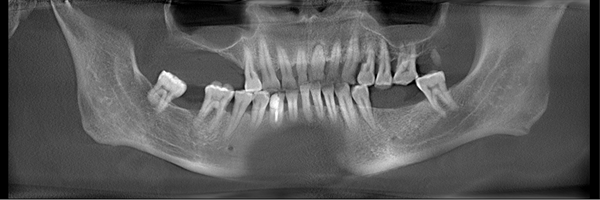

种牙前以为手术过程中会感觉到疼痛,结果轻松就完成了,并且手术后也没有什么不良反应,感觉非常好。麦芽种植专家根据CT拍片的牙槽骨数据和口腔健康情况分析,采用了微创无痛种植方案。这种手术最大的优点是只有3-4毫米微小切口,减少了肿痛和出血量,手术时间短,种植位置更准确,成功率也更高。